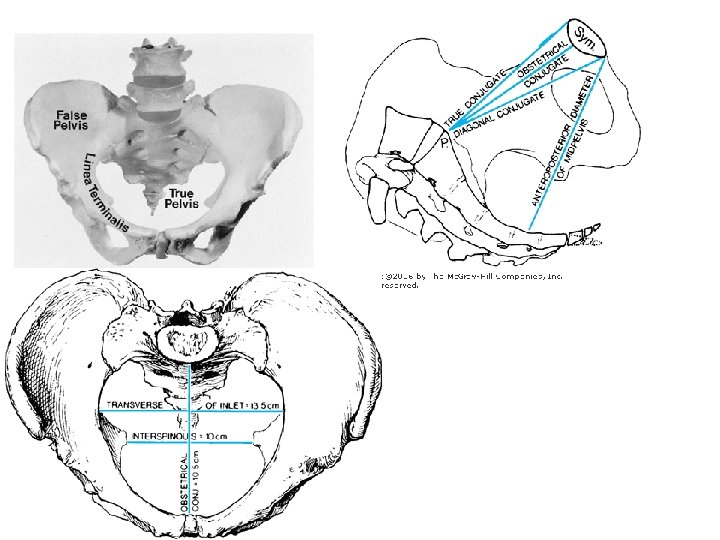

Bony pelvis • Composition: formed by paired hip bones, sacrum, coccyx, and their articulations • Two portions – Greater pelvis – Lesser pelvis • Terminal line ( pelvic inlet): formed by promontory of sacrum, arcuate line, pectin of pubis, pubic tubercle, upper border of pubic symphysis • Pelvic outlet: formed by tip of coccyx, sacrotuberous ligament, ischial tuberosity, ramus of ischium, inferior ramus of pubic symphysis

• Anatomical antero-posterior diameter (true conjugate) = 11 cm • Obstetric conjugate = 10. 5 cm (-2 cm from diagonal conj) • Diagonal conjugate = 12. 5 cm

Bony structures of a pelvis